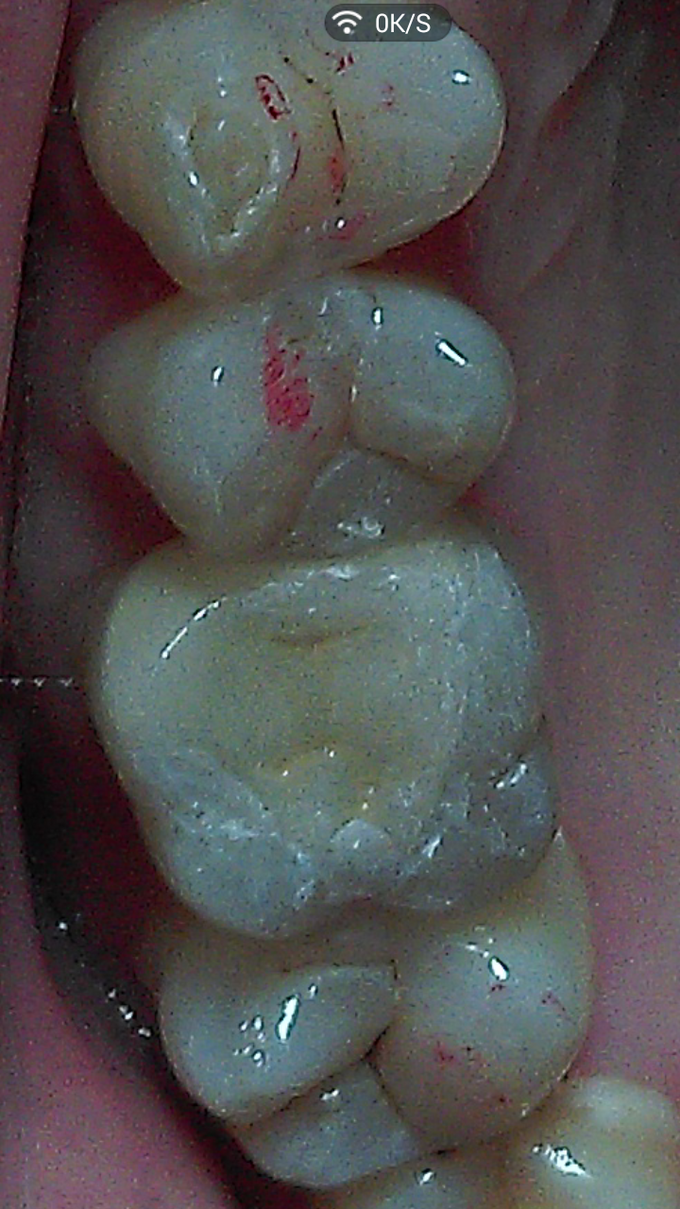

根据检查结果,提示,如冠修复,势必磨牙组织太多,更可怕的是,几乎全部釉质等坚硬组织可能去掉,这样基牙的抗力大大削弱。同时依据患者的要求,决定选用瓷嵌体修复。铸瓷价格偏高,病患没选择。 处理步骤: 1,牙周软组织准备,这一定要放在首位。去除结石,控制炎症。特别是判断生物学高度。避免后期的并发症。 2,硬组织准备:去尽腐质,薄壁弱尖,无基釉等。 3,寻找固位形,根管内,箱状等。 4,龈壁处理,这是最关键的部位,必要时使用“深部边缘提升”(Deep Margin Elevation,DME)。 5,垫底,填倒凹,结合流体树脂和通用树脂。 6,比色。本病例,因原牙体组织微发暗,色调不是太理想。 7,取精密印模。 7,试戴和粘固。

临床诊断不是太难。个人认为最关键的地方在以下几点: 1,牙周处理及生物学宽度考量。 2,硬组织的去除和保留。 3,比色有点难度。 4,粘接剂的选择。咱选用3M的小蜜蜂。当然用Varilink II最好。